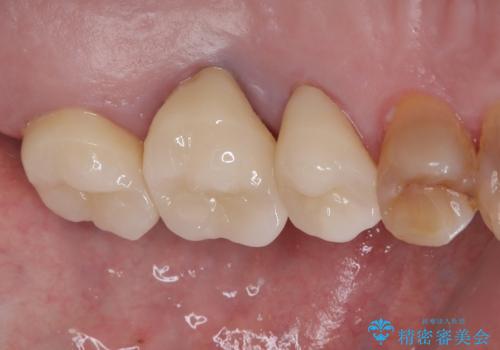

インプラント治療を含む精密審美治療

左上の小臼歯は根尖病巣が大きかったため、今後も定期的にレントゲンを撮り、経過観察していく予定です。